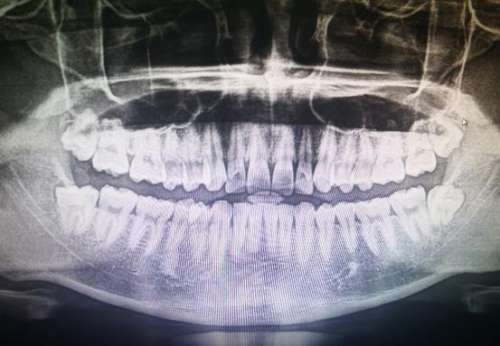

作為臨海市正規(guī)齒科醫(yī)院,麥爾口腔醫(yī)院擁有龐大的診療面積,達(dá)900余平方米。引進(jìn)了歐美先進(jìn)的口腔診療設(shè)備,涵蓋“MAC數(shù)字化數(shù)據(jù)采集”等多個(gè)板塊。強(qiáng)大的技術(shù)實(shí)力和完善的設(shè)備保障了診療質(zhì)量和效率。